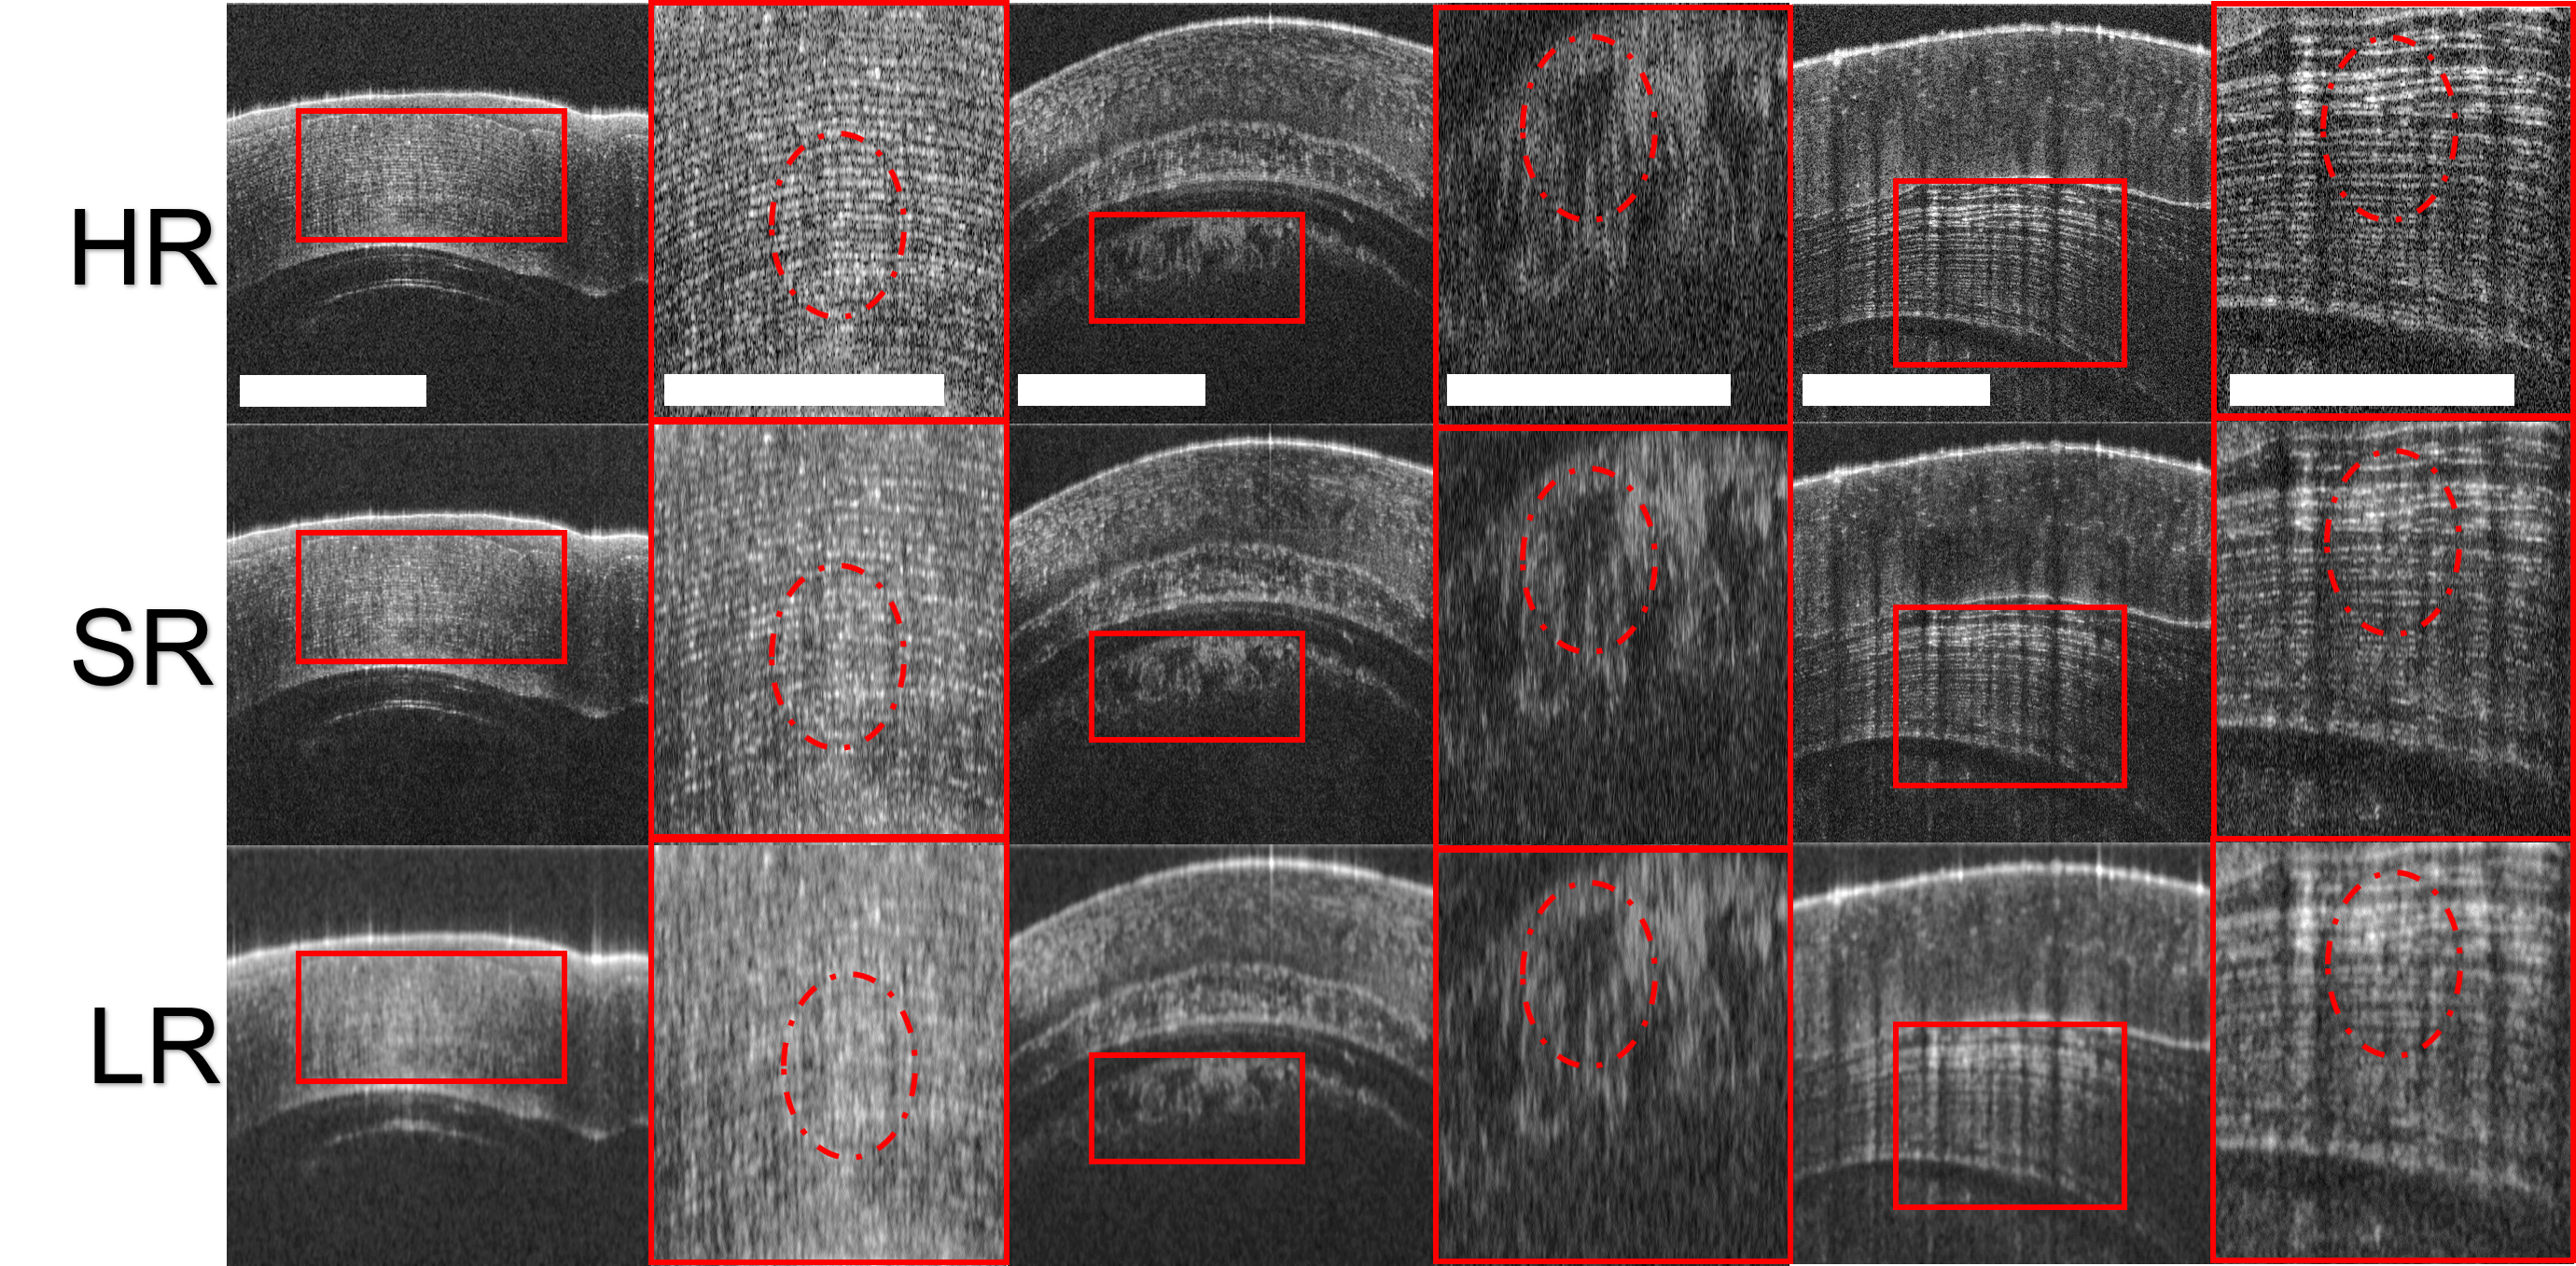

3.8 Application to super-resolve anterior segments of fish eye

Based on the setup in coronary imaging, we perform additional experiments on fish cornea using trained frequency-aware framework from previous section. We acquired the fish corneal OCT images using the same OCT system and imaging settings as the coronary dataset. We acquired three volumes of left and right fish eyes. Three representative OCT B-scans are used for the qualitative studies. The qualitative analysis of SR OCT images of fish corneal is shown in Fig 6. In particular, the dash circle in the first panel shows the alignment of corneal stroma is better resolved after super-resolving. The dash circle in the second panel highlights the iris region that is underneath the corneal regions. The dash circle in the third panel resolves the bownman’s layer in corneal region. Overall, our frequency-aware framework is capable of generating SR OCT fish corneal images with sharper and finer textures. Without retraining, our frequency-aware framework has the potential to be transferrable to OCT corneal images obtained from the same OCT system.

Another contribution lies in generalizability. Our preliminary study indicates great potential to be applied to multiple tissue types. We perform qualitative experiments on additional fish eye and rat eye dataset. Without retraining, our frequency-aware framework resolves anterior segments of fish eye, including corneal stroma, iris region, and downman’s layer, acquired from the same OCT system. With adequate retraining, our frequency-aware framework is capable of resolving LR OCT images acquired from different systems. From the qualitative analysis of a rat eye dataset acquired from a different OCT system, we resolve the boundary around the optical disc and within retinal regions, with adequate retraining.